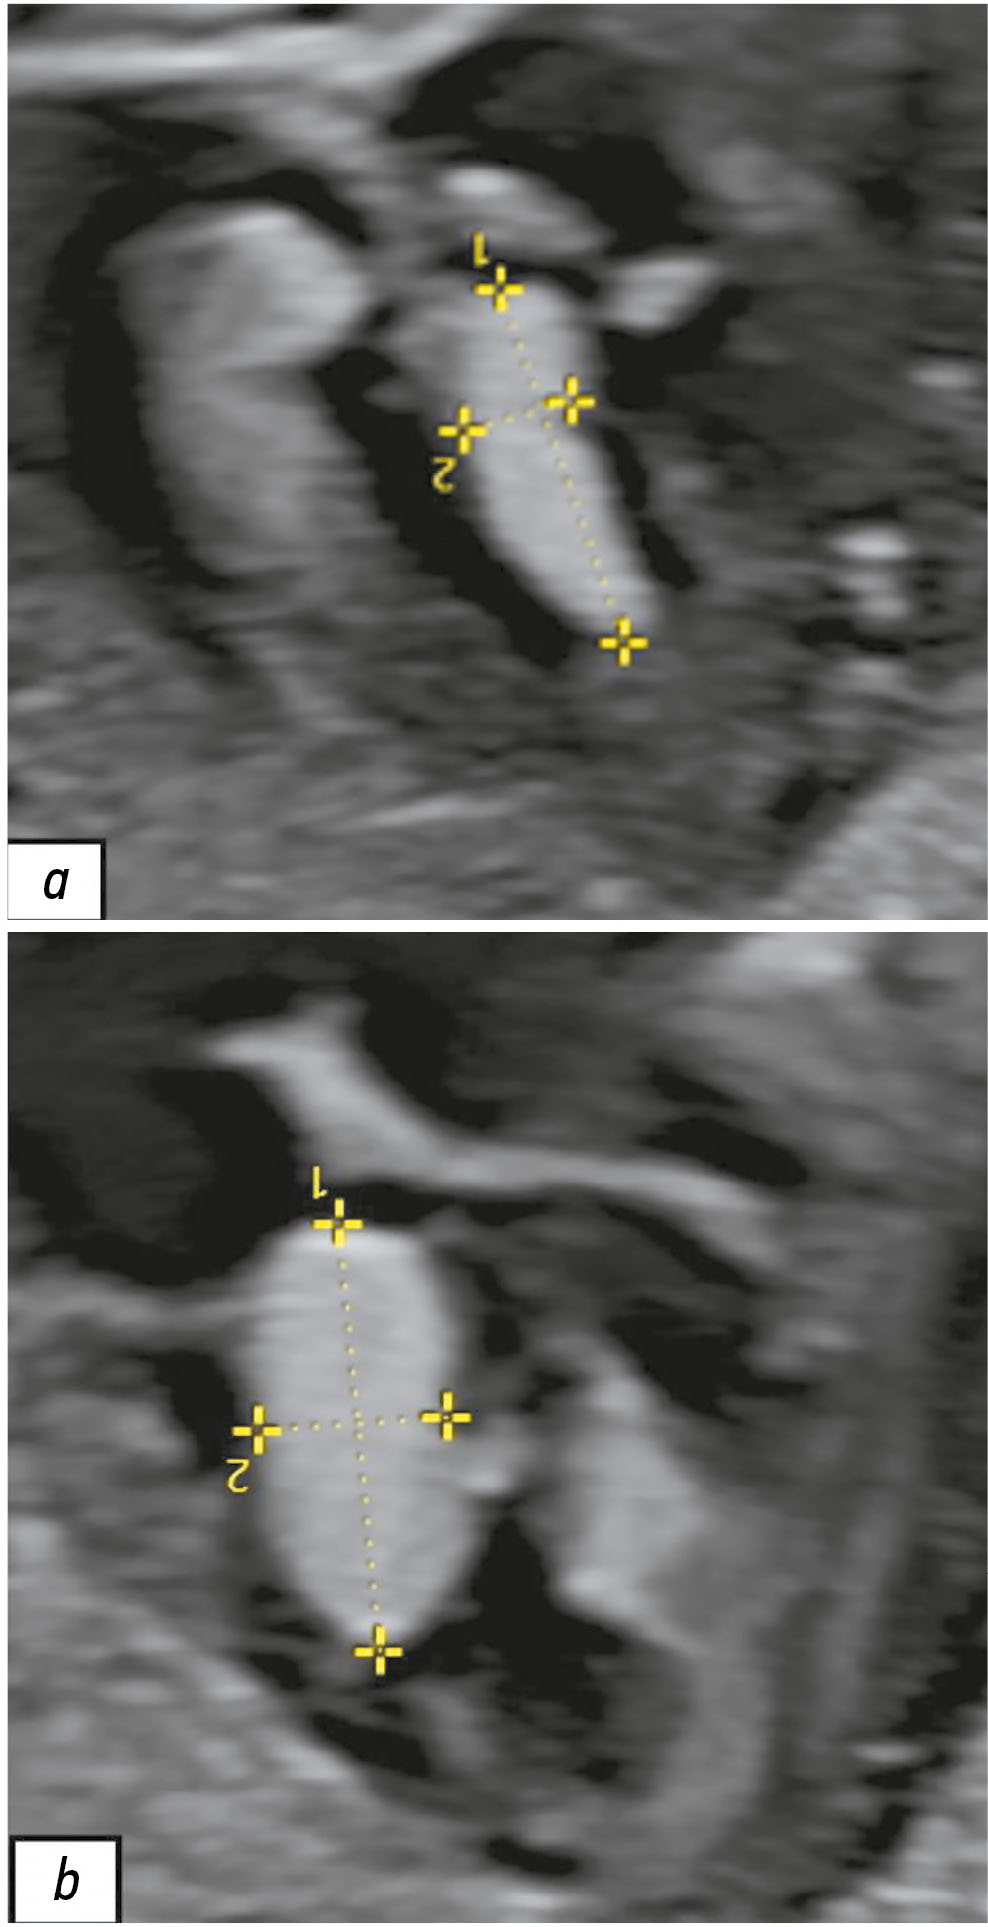

Hereditary transthyretin amyloidosis is a rare, progressive, systemic autosomal dominant disorder characterized by the extracellular deposition of insoluble amyloid fibrils in the peripheral nervous system, heart, and other organs. Among the specific signs of this condition, symptomatic spinal canal stenosis is prominent. Lipoprotein(a) is an atherogenic lipoprotein, and increased plasma concentrations are a significant risk factor for cardiovascular and cerebrovascular diseases. Data regarding the relationship between transthyretin amyloidosis and lipoprotein(a) levels are limited.

This article presents a clinical case of a patient with arterial hypertension, with blood pressure elevated to 150/90 mmHg for 5 years. Following a COVID-19 infection between June 2, 2021, and June 25, 2021, the patient experienced a marked increase in blood pressure to 290/150 mmHg; sharp left-sided chest pain lasting 20–30 minutes unrelated to physical activity, which was relieved with medication; and pain in the cervical and thoracic spine. Despite antihypertensive therapy, the patient’s blood pressure stabilized at 110/70 mmHg. Further evaluation revealed dyslipidemia, with increased low-density lipoprotein cholesterol levels at 4.53 mmol/L and lipoprotein(a) at 1.46 g/L. Doppler ultrasound revealed atherosclerosis in the extracranial parts of the brachiocephalic arteries, with up to 20% stenosis of the right internal carotid artery. Echocardiography showed thickening of the left ventricular wall, interatrial septum, and mitral valve leaflets, although the ejection fraction remained preserved. Magnetic resonance imaging of the spine revealed cervical spinal canal stenosis (C5–C6). Genetic testing identified a nucleotide sequence variant in the transthyretin gene (Chr18: 29171879 G>A, p. Arg5His) in the heterozygous state in the patient and her blood relatives. Specific anti-amyloid therapy with tafamidis was considered, and hypolipidemic therapy was initiated.

In patients with symptomatic spinal canal stenosis and left ventricular wall thickening, even in the presence of hypertension, comprehensive evaluation is crucial for the timely diagnosis and adequate management of amyloid cardiomyopathy. Thus, we describe the first reported clinical case of the combination of familial transthyretin amyloidosis and hyperlipoproteinemia(a).